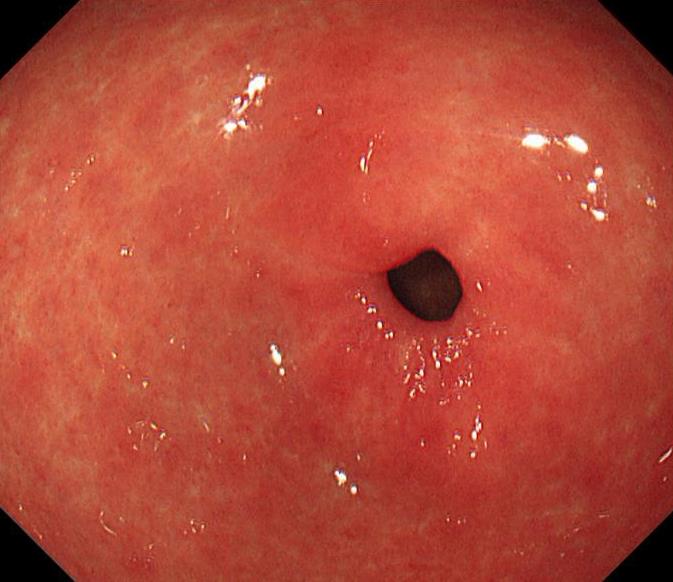

摘要:目的 探讨利那洛肽联合西甲硅油与复方聚乙二醇电解质散(PEG)对便秘患者肠道清洁效果的有效性和安全性。方法 采用前瞻性随机对照试验,通过单盲法,纳入2023年4月-2024年8月于该院消化内镜中心行结肠镜检查的便秘患者383例,随机分为常规组(128例)、实验A组(128例)和实验B组(127例)。常规组采用3 L PEG(Ⅰ)溶液,实验A组采用290 μg利那洛肽 + 2 L PEG溶液,实验B组采用290 μg利那洛肽 + 30 mL西甲硅油+2 L PEG溶液。比较3组患者的肠道准备效果[Boston肠道准备量表(BBPS)评分和去泡效果]、病变检出率、首次排便间隔时间、排便次数、盲肠插管成功率、进镜时间、退镜时间、不良反应发生率和重复检查意愿等。结果 3组患者BBPS评分比较,差异无统计学意义(P > 0.05);实验B组的去泡效果评分明显低于常规组和实验A组,差异均有统计学意义(P < 0.05);实验B组的病变总检出率和息肉检出率明显高于常规组和实验A组,差异均有统计学意义(P < 0.05);常规组的首次排便间隔时间明显长于实验A组和实验B组,差异均有统计学意义(P < 0.05);3组患者排便次数比较,差异无统计学意义(P > 0.05);3组患者盲肠插管成功率均为100.0%,进镜时间相当,差异均无统计学意义(P > 0.05);实验B组的退镜时间明显短于常规组和实验A组,差异均有统计学意义(P < 0.05);常规组腹胀腹痛发生率和不良反应总发生率明显高于实验A组和实验B组,差异均有统计学意义(P < 0.05);常规组重复检查意愿率明显低于实验A组和实验B组,差异均有统计学意义(P < 0.05)。结论 290 μg利那洛肽联合30 mL西甲硅油与2 L PEG溶液方案在便秘患者肠道准备上具有优势,较3 L PEG溶液和290 μg利那洛肽+2 L PEG溶液方案,可获得更好的肠道清洁效果,且安全性和患者重复检查意愿率高,可作为便秘患者肠道准备的推荐方案。